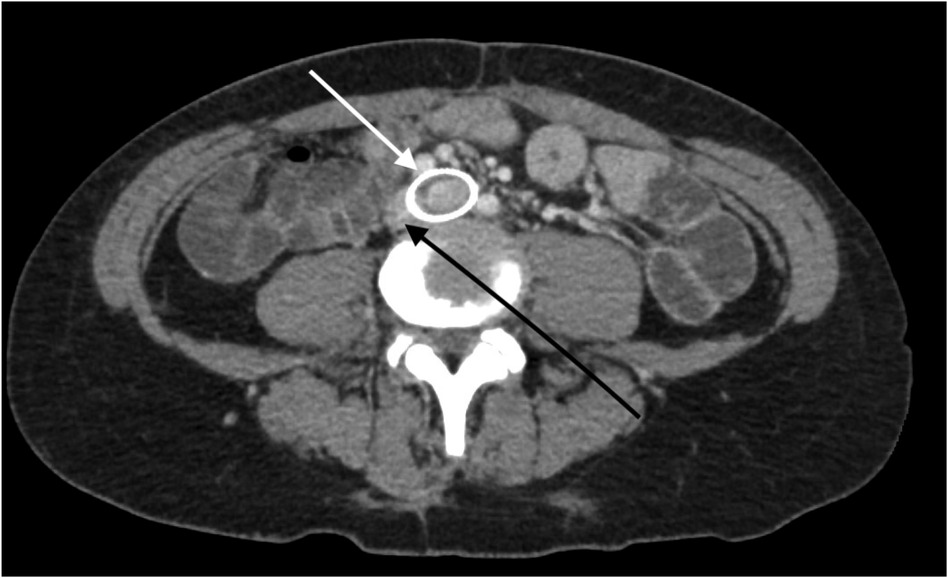

The patient underwent treatment at AMITA Hinsdale Hospital (Hinsdale, IL, USA). Under moderate sedation, the patient underwent traditional transcatheter venography (Figure 2). This, along with intravascular ultrasound (IVUS), confirmed significant (25) left common iliac vein stenosis by an overlying common iliac artery of greater than 50% (25) (Figure 3). She was initially treated with placement of a left iliac vein stent. Post procedure, she was prescribed clopidogrel for 30 days. 30–40 mm Hg waist-high compression hose were ordered, and she was advised to hydrate daily with 100 oz of electrolyte drinks. She underwent a routine clinical and imaging follow-up at 1 and 6 months. Confusion and dizzy spells were reported as alleviated at 1 month, but still some diminished cognitive clarity persisted. At 6 months, she reported improvement in cognition to a point where she reenrolled in graduate studies and resumed driving. According to her neurologist, she was having significantly fewer headaches and fatigue was reported to be reduced. Slight dizziness persisted, and she was started on a short course of midodrine. Dyspareunia persisted. She was subsequently administered a percutaneous ultrasound-guided injection of the vaginal wall and vulvar varices with 0.5% sotradecol foam using the Tessari technique (13). There were no immediate procedural complications, and her dyspareunia resolved after 3 months. At 12 months after iliac vein stenting, repeat neuropsychiatric testing (with the same examiner) showed her memory at the 95th percentile. Her full-scale IQ increased modestly. The Beck Depression Inventory II score moved to the normal range. The overall impression was “normal exam” (Supplementary Table 1). At 18 months after stenting, her dizziness returned, and dyspareunia reappeared. An ultrasound suggested a developing right iliac vein stenosis. Subsequently, a CT venogram showed the left stent pressing upon an already partially compressed right common iliac vein (Figure 4). She then underwent placement of a right-sided iliac vein stent. She was again prescribed clopidogrel, but for only 3 months, and again advised to drink 100 oz electrolyte solution daily and wear waist-high compression hose.

Figure 4

CT scan image of the abdomen showing a cross-sectional view. Two arrows point to specific circular areas of interest, highlighting anatomical or pathological features. Surrounding tissues and structures are visible for context.

Figure 4. A CT venogram in the axial plane shows a stented left common iliac vein (white arrow) and the adjacent compressed right common iliac vein (black arrow).